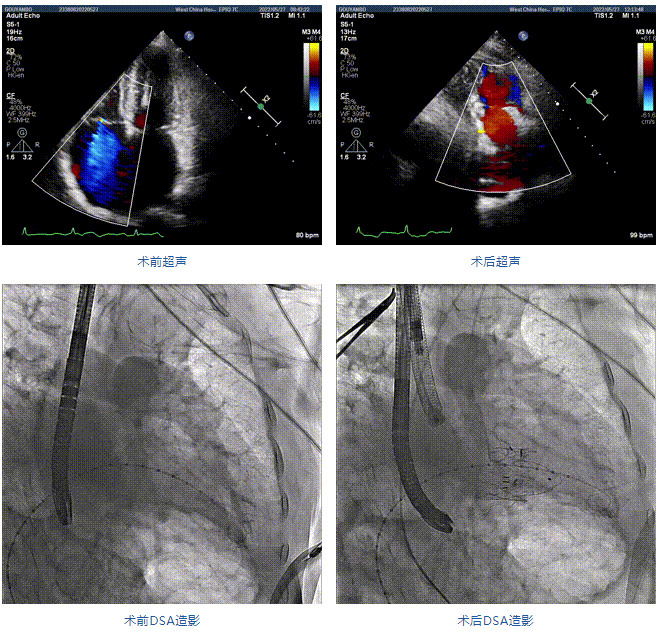

89歲男性。術(shù)前超聲報告顯示:雙房增大,左室壁肥厚,主、肺動脈增寬,三尖瓣重度反流。

團(tuán)隊(duì)前期經(jīng)過多次討論,制定了周密的手術(shù)策略和預(yù)案。由于患者已是近九旬的超高齡老人,傳統(tǒng)外科開胸手術(shù)風(fēng)險極高,純介入經(jīng)血管三尖瓣替換能夠明顯減少創(chuàng)傷。術(shù)中陳茂及馮沅教授結(jié)合體表定位在造影指示下精準(zhǔn)穿刺右側(cè)頸靜脈并預(yù)置兩把血管縫合器。成功建立經(jīng)皮血管入路后在食道超聲和DSA的引導(dǎo)下順利完成人工瓣膜植入,術(shù)后超聲和造影顯示人工三尖瓣同軸性良好,瓣架固定牢靠,無反流和瓣周漏,平均跨瓣壓差降為1mmHg。術(shù)畢收緊預(yù)置的血管縫合器縫線完成止血,縫合效果滿意,在手術(shù)室即刻拔除氣管插管。